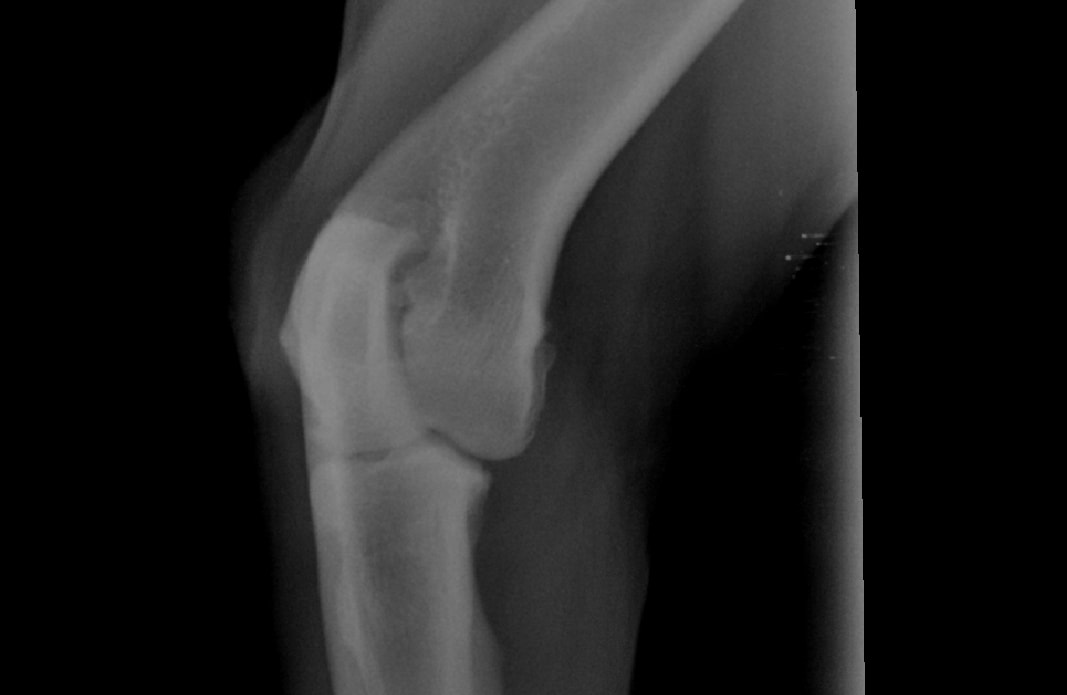

Hi Again, I asked a question recently regarding my rottie - We had a 2nd opinion at a specialist. they also cannot tell us what is wrong. They took xrays again and said it is inflamed. so they put him again on anti inflams - they said he has to go back in a month because they suspect bone cancer - I don't understand why they cannot test for it. they suspect bone cancer in his shoulder. its either that or his cartlidge is damaged. I don't want to wait 4 weeks and do nothing. please help.

The bone lesion is small on the xray. Diagnosing bone cancer can sometimes be difficult on the smaller lesions. A bone biopsy is something they might consider. Your specialist is likely waiting to see if the changes become more pronounced in order to obtain a better sample. A CT scan should be considered as well. This breed is predisposed to certain cancers and we see bone cancer commonly in this breed. Please let me know if you have any other questions or concerns.